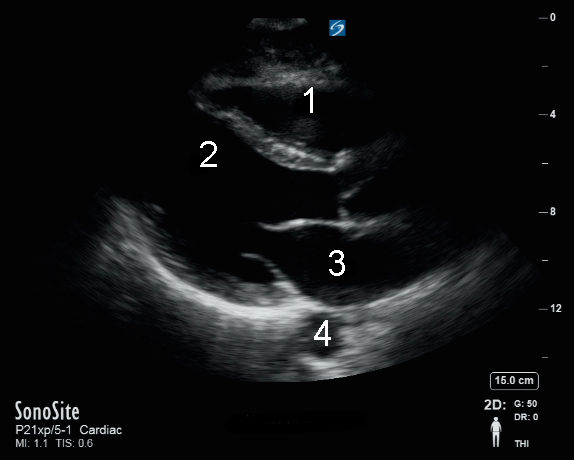

心脏胸骨旁长轴 (PLAX) 视图图像

右心室 (RV)

左心室 (LV)

左心房 (LA)

主动脉 (Ao)